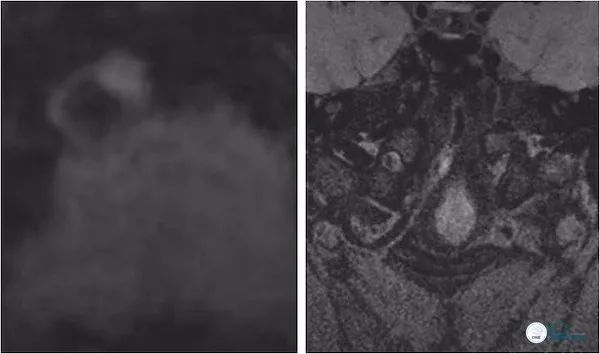

高分辨核磁:右椎动脉V4段斑块形成并狭窄(图10)。

图10